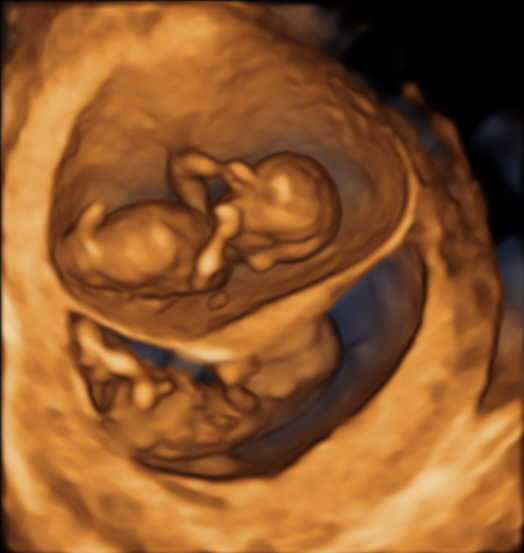

Zwei Babys aber nur eine Plazenta: Früher Ultraschall bei Zwillingsschwangerschaft äußerst wichtig

Berlin – Zwillingsschwangerschaften gelten immer als Risikoschwangerschaften. Das Risiko für Komplikationen erhöht sich, wenn sich beide Zwillinge eine Plazenta – auch Mutterkuchen genannt – teilen. Dies können Ärzte im Ultraschall jedoch nur in der Frühschwangerschaft sicher feststellen, belegt eine aktuelle Studie aus den USA. Die Deutsche Gesellschaft für Ultraschall in der Medizin (DEGUM) empfiehlt Schwangeren, die erste Vorsorge-Ultraschalluntersuchung zwischen der 9ten und 12ten Schwangerschaftswoche unbedingt wahrzunehmen.

„Eine falsche Bestimmung der Chorionizität kann fatale Folgen haben“, warnt Heling. Denn die Plazenta versorgt die heranwachsenden Föten mit Nährstoffen und Sauerstoff. Teilen sich zwei Kinder eine Plazenta – dies ist bei den meisten eineiigen Zwillingen der Fall – ist das Risiko für Wachstumsverzögerungen, Früh- oder Totgeburt deutlich erhöht. Auch das sogenannte feto-fetale Transfusionssyndrom (FFTS) zählt zu den Komplikationen, die nur monochoriotische Zwillinge betreffen. Hierbei stehen die kindlichen Blutkreisläufe miteinander in Verbindung. Eines der Kinder wird besser mit Blut versorgt als das andere – ein lebensbedrohlicher Zustand für beide Kinder. "Wird das FFTS frühzeitig erkannt, besteht die Möglichkeit, die Gefäßverbindungen per Laser vorgeburtlich zu verschließen oder die Geburt vorzeitig einzuleiten", erklärt Heling.